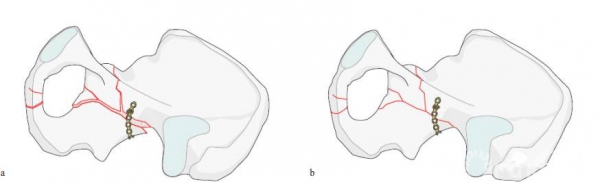

2.第二块钢板

内侧钢板,该钢板需要过预弯。通过钢板的挤压来复位内移的方形区,沿骨盆缘的内侧进行置放。

当方形区有较大独立骨块的时候,也可以采用T形钢板。

需要注意螺钉不要进入关节

3.第三块钢板、髂坐钢板

来进行后柱的骨折复位,同时可以防止方形区的移位。这三块钢板可单独使用,也可同时使用,根据骨折类型决定。

1+2

1+3